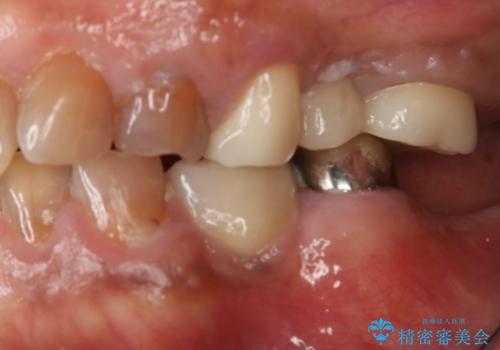

露髄や痛みなどの症状も出ず、経過は良好です。